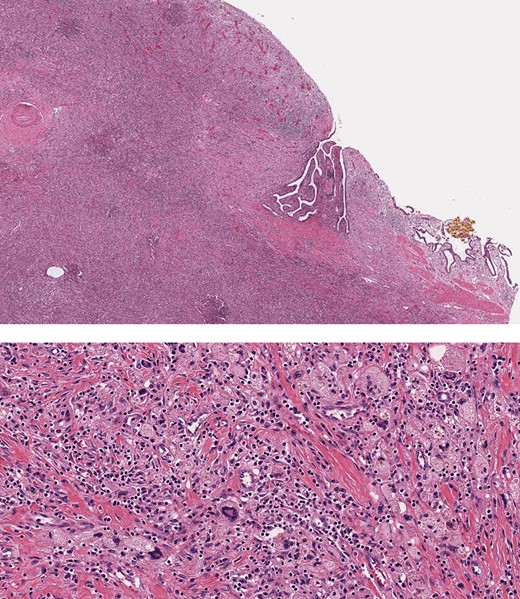

Intraoperatively, the surface of the liver was noted to be quite inflamed. There were dense pericholecystic adhesions, and the gallbladder was diffusely thickened. A hard mass with surrounding inflammatory and fibrotic changes was encountered in segment IV. After mobilizing the liver and controlling all hilar structures, in addition to Doppler confirmation of right hepatic artery flow, an extended left hepatectomy was performed. The right hepatic artery was carefully dissected off the mass, and the left liver including segments 5 and 8 as well as the caudate lobe was resected (Fig. 4). We were able to preserve the main bile duct. Pathology subsequently revealed XGC extending into the hepatic parenchyma (Fig. 5). After an uneventful post-operative course patient was discharged to extended care facility in stable condition 8 days after his surgery.

Histopathology, showing transmural inflammatory process in the gallbladder with mucosal ulceration (top) and the mass lesion composed of sheets of foamy histiocytes admixed with plasma cells, lymphocytes, collagen fibers and scattered giant cells (bottom).